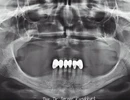

Diş Eksikliği

Ağız diş ve çene cerrahisi